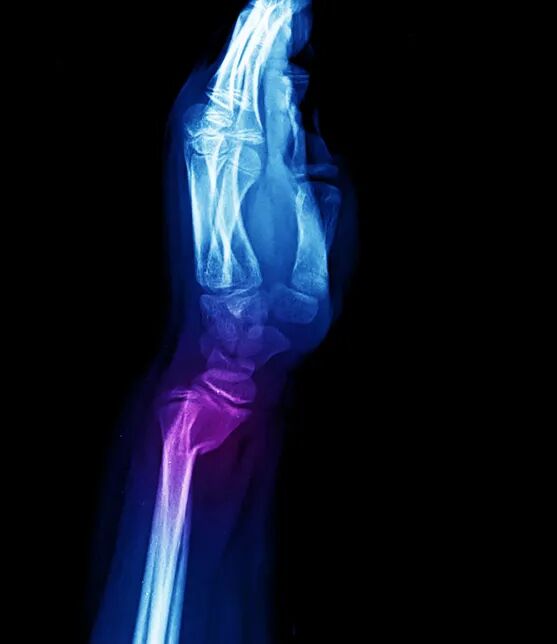

银叉样畸形X线图像

X线片正侧位示柯氏骨折

典型畸形姿态即侧面看呈「 银叉 」畸形,正面看呈「 枪刺样 」畸形。X 线可见骨折远端向桡、背侧移位,近端向掌侧移位。